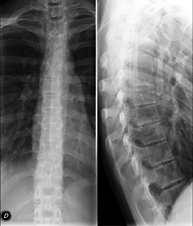

- Columna

- RX Columna cervical

Tècnica que usa els raigs X a través de la qual s'obtenen imatges de la columna cervical per al seu estudi. Indicacions: traumatisme, dolor cervical. - RX Columna dorsal

Tècnica que usa els raigs X a través de la qual s'obtenen imatges de la columna dorsal per al seu estudi. Indicacions: traumatisme, mal d'esquena. - RX Columna lumbar

Tècnica que usa els raigs X a través de la qual s'obtenen imatges de la columna lumbar per al seu estudi. Indicacions: ciàtica, traumatisme, dolor lumbar. - RX Sacre-còccix

Tècnica que usa els raigs X a través de la qual s'obtenen imatges del sacre i del còccix per al seu estudi. Indicacions: traumatisme, dolor sacre o coccigi. - Telerradiologia columna

Tècnica que usa els raigs X a través de la qual s'obtenen imatges de tota la columna vertebral per al seu estudi, amb la valoració especialment de la presència d'escoliosi i dismetries pèlviques.